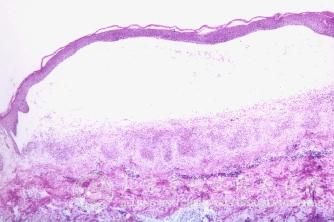

男性同性恋生殖器疱疹症状特点有:男性同性恋可出现肛门直肠HSV-2感染,其发病率仅次于淋球菌所致的肛门直肠炎,临床表现为肛门直肠疼痛、便秘、分泌物增加和里急后重,肛周可有疱疹性溃疡,乙状结肠镜检常见直肠下段粘膜充血、出血和溃疡。